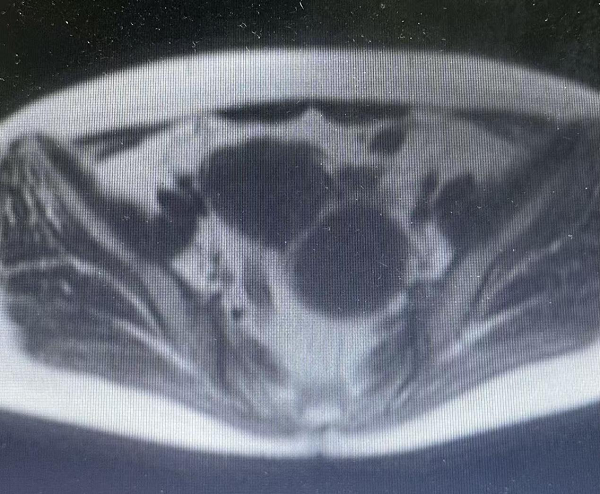

腹腔镜辅助下经阴道全子宫切除术(LAVH)(四级手术):近日,我院妇产科主任医师袁树华及副主任医师周丽萍组成的妇科团队成功为一名老年多发性子宫肌瘤患者实施腹腔镜辅助下经阴道全子宫切除术(LAVH)。患者子宫多发肌瘤,增大如孕3月余,直径7cm、5cm至2cm大小瘤体8个。传统术式需开腹留下长疤,而本次手术仅借助腹腔镜辅助,经女性自然腔道完整切除子宫及瘤体,腹部切口(1个脐孔和2个直径0.5cm穿刺孔。术后患者恢复良好,第二天即下床活动,无并发症,目前已顺利出院。该术式兼具腹腔镜的清晰视野与经阴道手术的无痕优势,是非脱垂子宫行子宫切除术微创治疗的理想选择。我院妇科开展此项技术,为女性健康保驾护航,不留“心疤”。